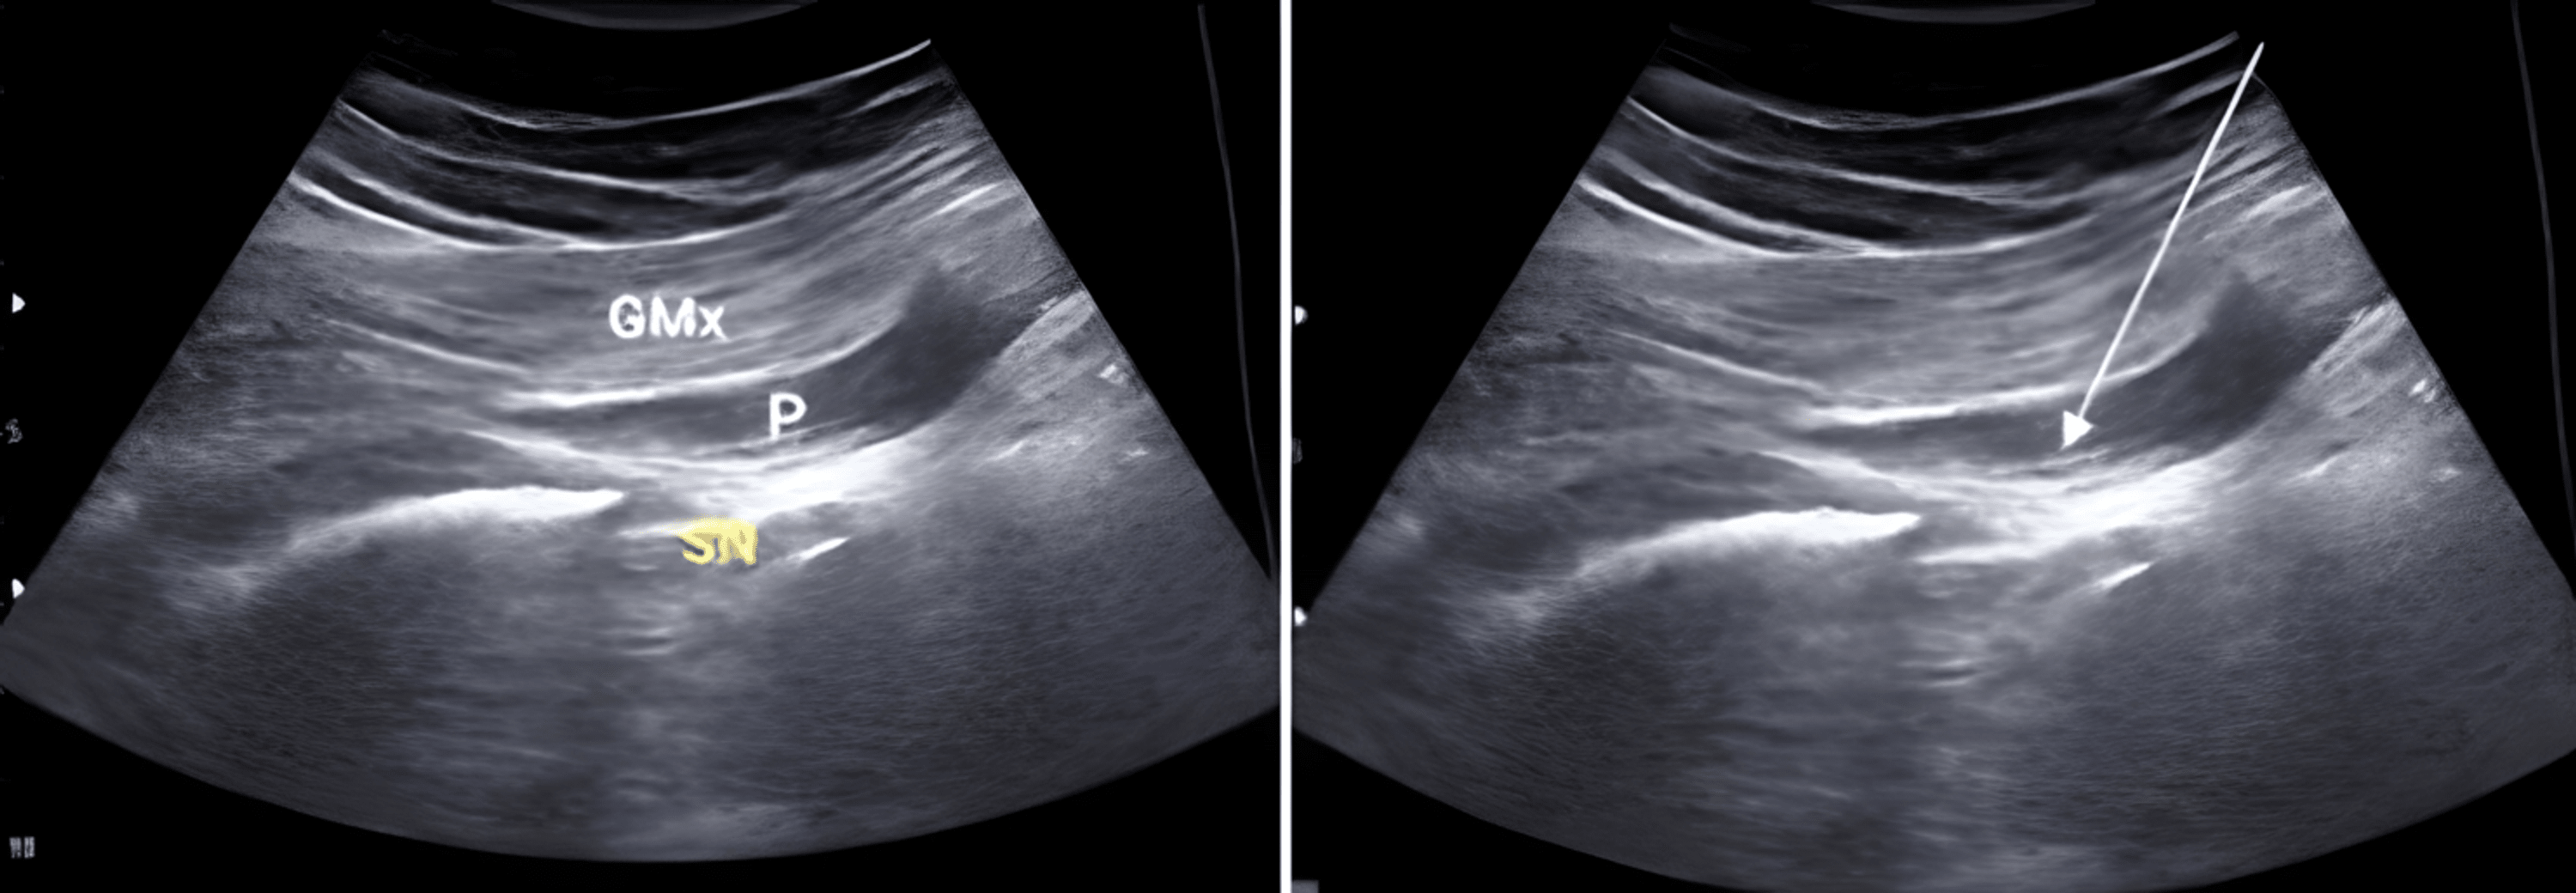

Cureus Evaluation of the Efficacy of UltrasoundGuided Dry Needling Therapy and Exercise in Does Dry Needling Work For Piriformis Syndrome dry needling or intramuscular stimulation (ims) of the piriformis muscle is an effective treatment for piriformis syndrome, which is a condition that causes. does dry needling help piriformis syndrome? It occurs when the piriformis muscle presses. the concern with needle therapies of deeper muscles that are not directly. piriformis syndrome causes pain or numbness in your. Does Dry Needling Work For Piriformis Syndrome.